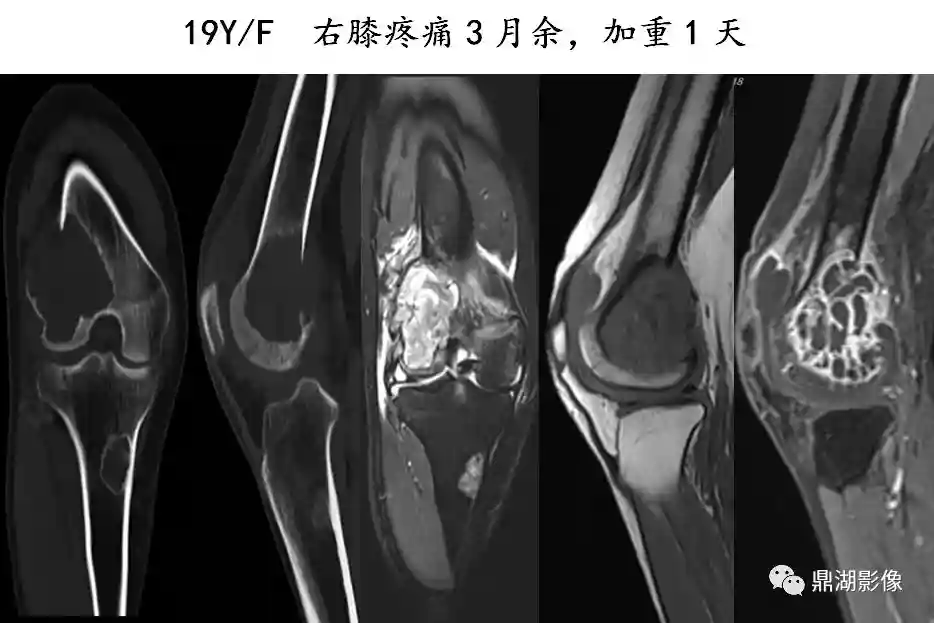

骨巨细胞瘤

是一种局部侵袭性肿瘤,大部分为良性,部分生长活跃,也有少数一开始就是恶性

男女发病率相近,好发年龄是20-40岁

好发于骨骺板已闭合的四肢长骨骨端,尤其是股骨远端、胫骨近端和桡骨远端

膨胀性多房性偏心性骨破坏,横向生长

分房状或皂泡状,骨破坏区无钙化和骨化影